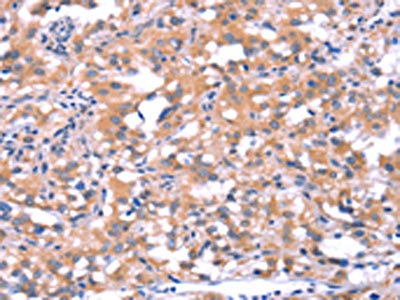

The image on the left is immunohistochemistry of paraffin-embedded Human thyroid cancer tissue using CSB-PA592424(FAT1 Antibody) at dilution 1/40, on the right is treated with synthetic peptide. (Original magnification: ×200)